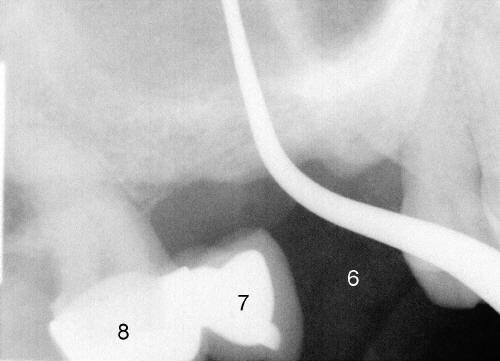

老汪:谢谢及时答复,右上七,右下五,六今后均需要做植牙,但是在美国一年牙科保险仅供做一个植牙。这位病人今年保险钱几乎用光了。右上七是牙桥中间部分(pontic),再附图一张,让您了解之前情况(右上六刚刚拔除,与上颌窦相通,挖匙进入上颌窦)。我很少做联冠,除非其中一个植牙太不争气。